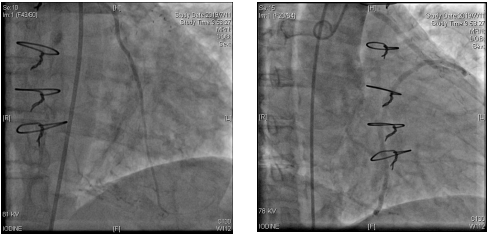

冠脉造影:

LIMA-LAD桥血管通畅,升主动脉造影显示:AO-SVG-D1-LCX-RCA桥血管通畅。